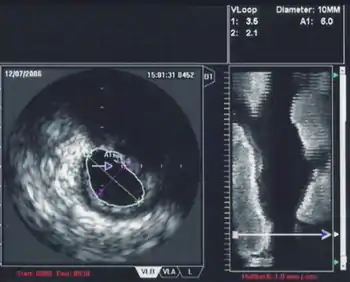

Intravascular ultrasound

Intravascular ultrasound, also known as a percutaneous echocardiogram is an imaging methodology using specially designed, long, thin, complex manufactured catheters attached to computerized ultrasound equipment to visualize the lumen and the interior wall of blood vessels.